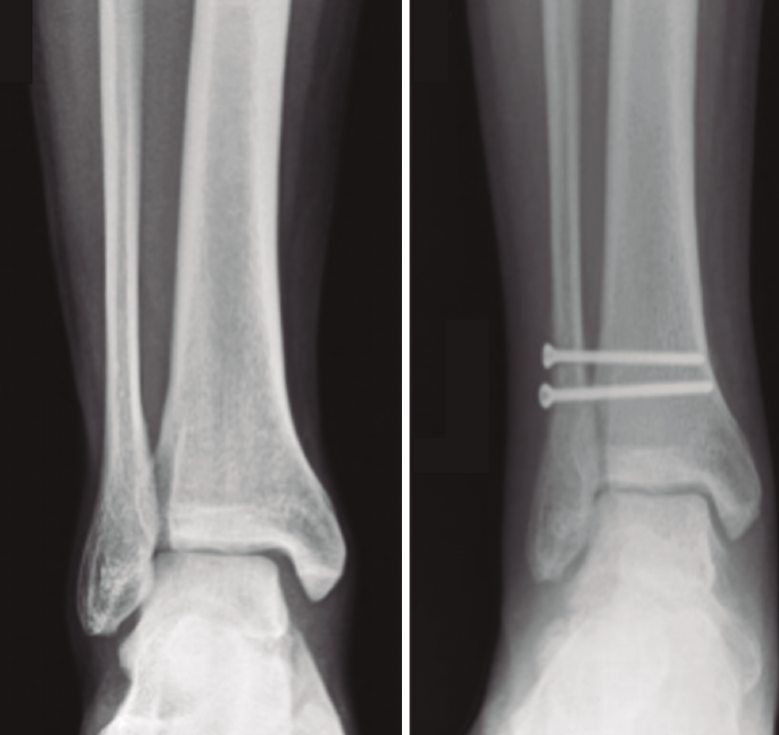

El método de tratamiento convencional suele ser la fijación de la sindesmosis con un tornillo de cortical a través del peroné situado a 2 o 3 cm por encima de la línea articular para evitar lesiones de los ligamentos y angulado de 20 a 30° anterior y medial(14,15). Se ha demostrado que 2 tornillos ofrecen mayor resistencia que un tornillo simple y que los tornillos de 4,5 mm son más resistentes que los de 3,5 mm. Más de 2 tornillos o de mayor diámetro no son aconsejables, ya que pueden provocar una fractura del peroné(2). Según lo publicado hasta ahora, no hay diferencias significativas entre el paso de 3 o 4 corticales. La carga completa no se recomienda hasta al menos 2 meses, una vez retirado el tornillo, para evitar roturas o síntomas dolorosos en la articulación del tobillo. Si bien está en discusión, ya que no parece haber diferencia significativa en el resultado funcional entre los pacientes que se sometieron a la extracción de rutina del tornillo transindesmal y los pacientes en los que el tornillo solo se extrajo en caso de implantes sintomáticos(16)(Figura 3).

Figura 3. Fijación rígida con tornillos.